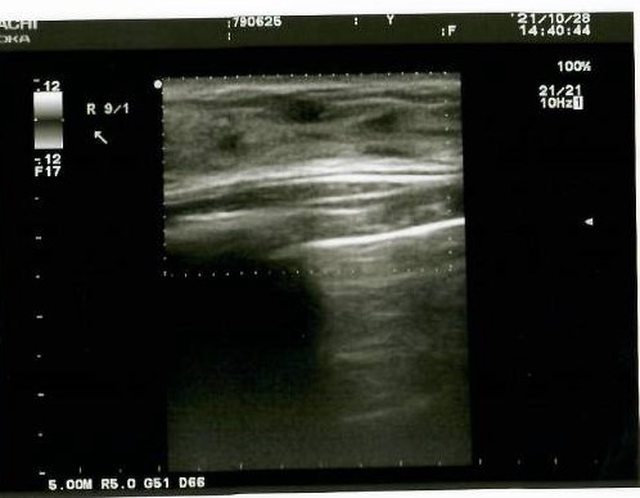

透過儀器的檢查發現在右側乳房有一個纖維囊腫

https://i.imgur.com/kEaJJT4.jpg

雖然不是看得很明白 但是跟左邊胸部的超音波畫面比起來確實多了東西